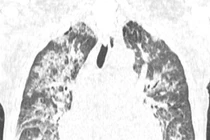

Ở Anh với khoảng 2 triệu lượt truyền, đã ghi nhận 59 ca tử vong liên quan tới truyền máu. Hơn một nửa trong số đó liên quan tới các tổn thương ở phổi.

Truyền máu vừa có thể cứu sống người bệnh nhưng cũng mang theo rủi ro ở từng lần truyền máu. Theo báo cáo giám sát tai biến truyền máu quốc gia (SHOT) của Vương quốc Anh, năm 2024 ở Anh, với khoảng 2 triệu lượt truyền, đã ghi nhận 59 ca tử vong liên quan tới truyền máu và hơn một nửa trong số đó liên quan tới các tổn thương ở phổi.